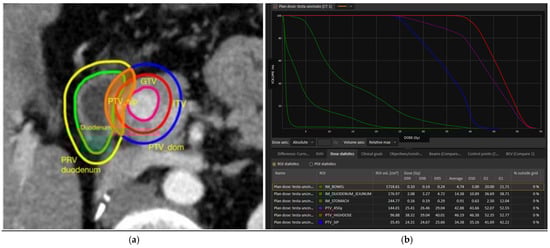

Impact of Dosimetric Parameters on Tumor Control in Stereotactic Radiotherapy for Pancreatic Cancer: A Prospective Study on 104 Patients Treated with Simultaneous Integrated Protection (SIP)

by Marco Lorenzo Bonù, Jacopo Balduzzi, Gloria Pedersoli, Dario Moneghini, Marco Ramera, Nazario Portolani, Jacopo Andreuccetti, Luigi Grazioli, Barbara Frittoli, Sarah Molfino, Anna Maria Bozzola, Maria Teresa Cefaratti, Eneida Mataj, Giulia Volpi, Luigi Spiazzi, Federica Saiani, Alfredo Fiume, Cesare Tomasi, Vittorio Morelli, Paola Vitali, Francesco Frassine, Luca Triggiani, Andrea Guerini, Davide Tomasini, Fabrizia Terraneo, Domenico Della Casa, Fernando Barbera, Stefano Maria Magrini and Michela Buglioneadd Show full author list remove Hide full author list

Cancers 2025, 17(22), 3617; https://doi.org/10.3390/cancers17223617 - 10 Nov 2025

Background: One of the challenges in treating pancreatic ductal adenocarcinoma (PDAC) with stereotactic radiotherapy (SRT) is to manage lesions abutted to the duodenum, bowel and stomach. Simultaneous integrated protection (SIP) is one of the proposed approaches to increase plan reproducibility and quality. [...] Read more.

Background: One of the challenges in treating pancreatic ductal adenocarcinoma (PDAC) with stereotactic radiotherapy (SRT) is to manage lesions abutted to the duodenum, bowel and stomach. Simultaneous integrated protection (SIP) is one of the proposed approaches to increase plan reproducibility and quality. However, no clinical data are available regarding the dosimetric objectives impacting local control probability. Methods: This is a prospective, single-arm study. Key inclusion criteria were as follows: PDAC histology; tumor abutment with duodenum, stomach, or small bowel; and SRT schedule consisting of 45 Gy in six fractions. Delineation of the PTV overlapped with critical OARs (PTV_SIP) and PTV outside critical OARs (PTV_Dominant) was mandatory. Dose constraints were as follows: (near) maximum dose, D2cc, and D20cc to critical OARs 38 Gy, 32 Gy, and 24 Gy, respectively. This study was designed to prospectively investigate the main clinical and dosimetric parameters impacting freedom from local recurrence (FFLR). Results: From June 2019 to January 2024, 104 patients were enrolled. One-year FFLR was 91.7%. Fifteen events of local failure occurred (17.6%). Mapping of local relapses showed a relapse inside the PTV_SIP area in nine patients and outside the PTV_SIP in six cases (NS). Whole PTV > 69 cc, PTV_SIP > 4 cc, PTV-SIP/whole PTV ratio > 7%, (near) Dmin to PTV_SIP < 25 Gy, mean dose to PTV_SIP < 28 Gy, and (near) Dmin to PTV_Dominant < 29 Gy were associated with worse FFLR. Multivariable analysis showed PTV_SIP absolute volume of more than 4 cc, mean dose to PTV_SIP < 28 Gy and whole PTV > 69 cc were independently related to worse FFLR. One case of acute G4 toxicity and two cases of acute G3 toxicity occurred, with two late toxicity deaths not certainly due to treatment. Conclusions: In this prospective study, SIP planning strategy with six fractions is safe and effective in pancreatic targets with critical contact with critical OARs. Given its potential advantages, SIP planning is a potential innovative strategy that should be compared to standard SRT planning in an ad hoc trial design. Full article